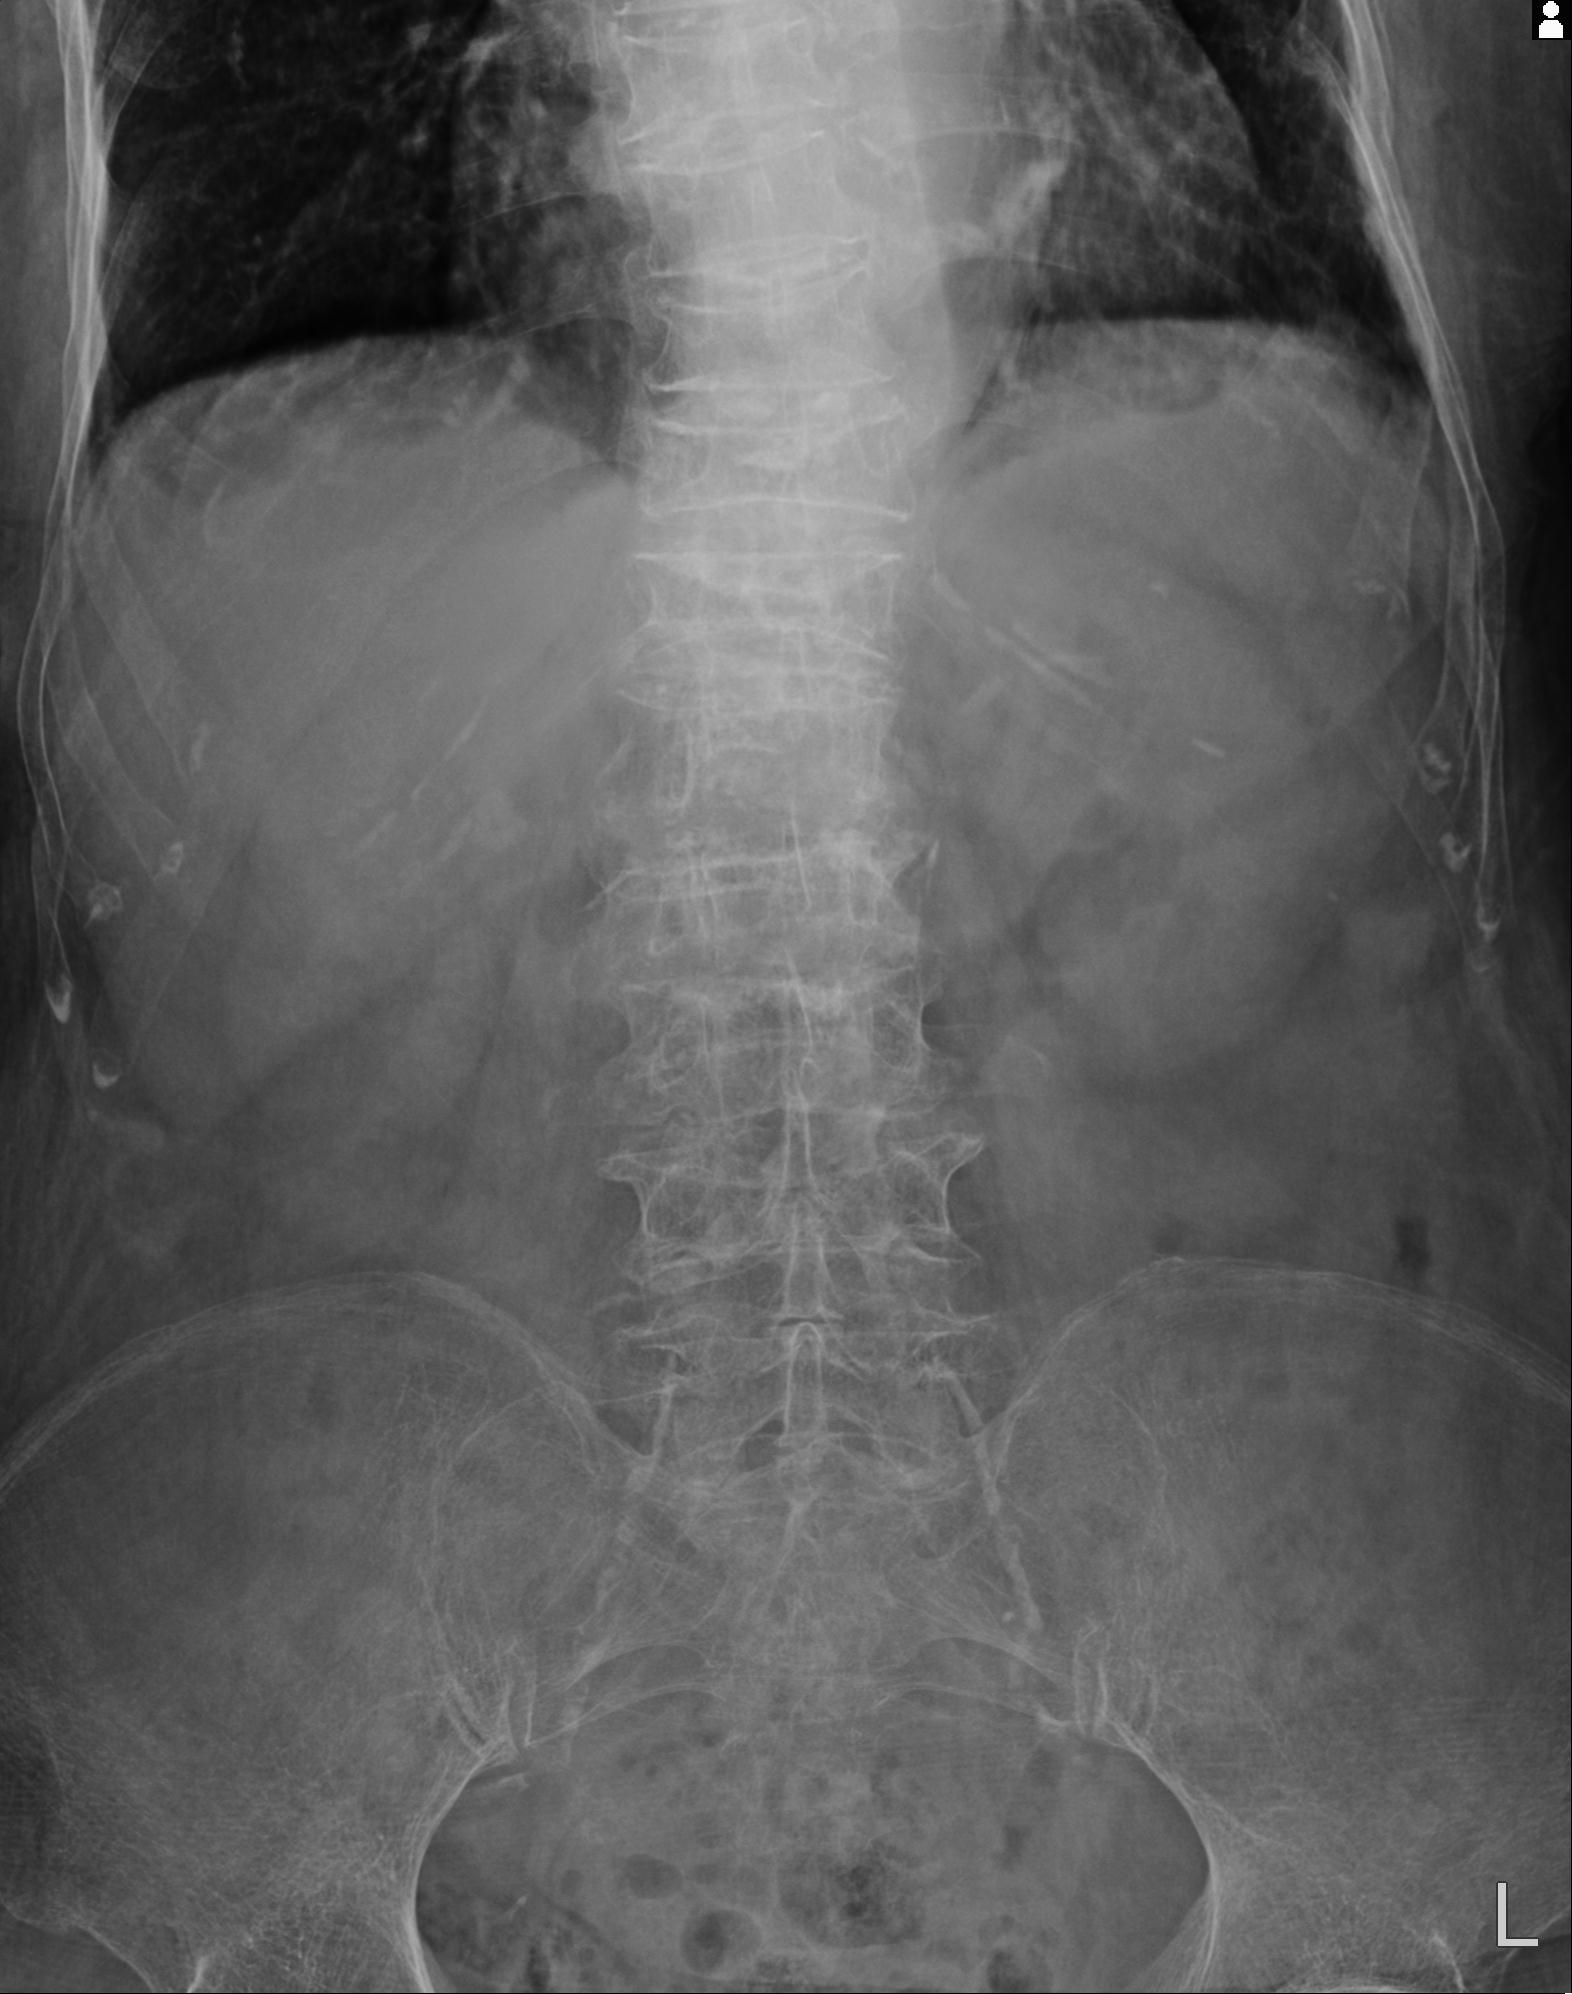

100703 1/27 両股正面+軸 1/29 両股正面+軸 94歳女性 パンソンロン